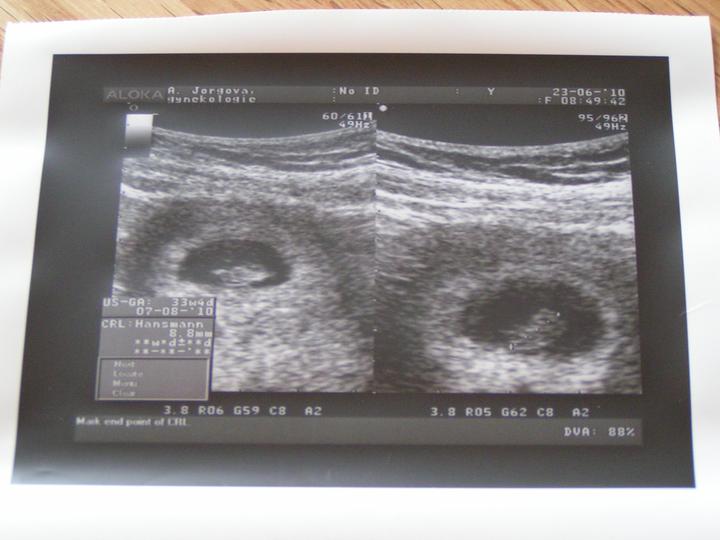

tak dnešní kontrola dopadla výborně, odpovídáme 11+1tt 🙂